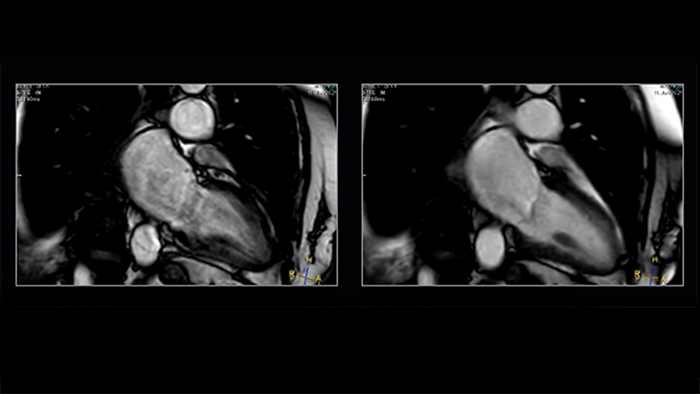

Shorter-breath holds are particularly impactful for patients who cannot manage the length of the breath-hold instruction. Mr. Strachan commented, “using Compressed SENSE sometimes pulls a non-diagnostic study into being a diagnostic study. That itself is very valuable.” For example, see Fig. 1

Figure 1. Shortening acquisition and denoising from C-SENSE provides confidence in long-axis cine of a patient with atrial fibrillation. Left to right: SENSE x2, C-SENSE x4

The impact of motion is reduced by Compressed SENSE in two ways. As well as allowing data to be acquired in a shorter duration [2] (so less movement [2] has occurred during readout), it also intrinsically includes denoising, which is a feature of any compressed sensing based acceleration method. If a motion artefact has a similar appearance to the smeared-aliasing which is deliberately produced by the incoherent undersampling which Compressed SENSE employs, the reconstruction may filter some of it out.